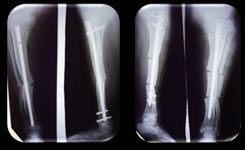

Wykorzystanie systemu Charfix

Do operacji

Po 5 miesiącach od początku operatywnego

leczenia

Dzięki mocnej metalokonstrukcji jest możliwość szybszego

obciążenia na kończyny